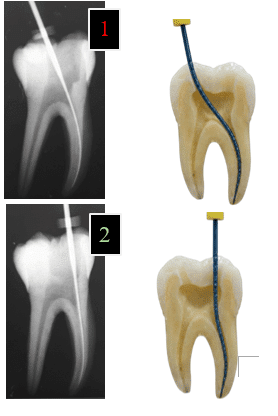

Take radiographs to guide preparation and verify position.

Protocol: Use a preoperative radiograph for anatomy and an immediate post-access radiograph to check depth and location relative to orifices.